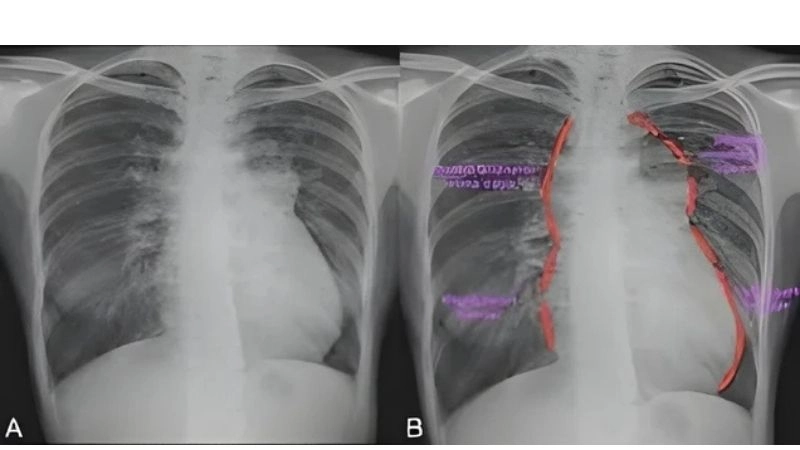

Images visual examples of total anomalous pulmonary venous return (TAPVR)

Total anomalous pulmonary venous return (TAPVR) is a rare congenital heart defect where pulmonary veins drain into the wrong heart chamber, impairing oxygen delivery and requiring surgical correction.